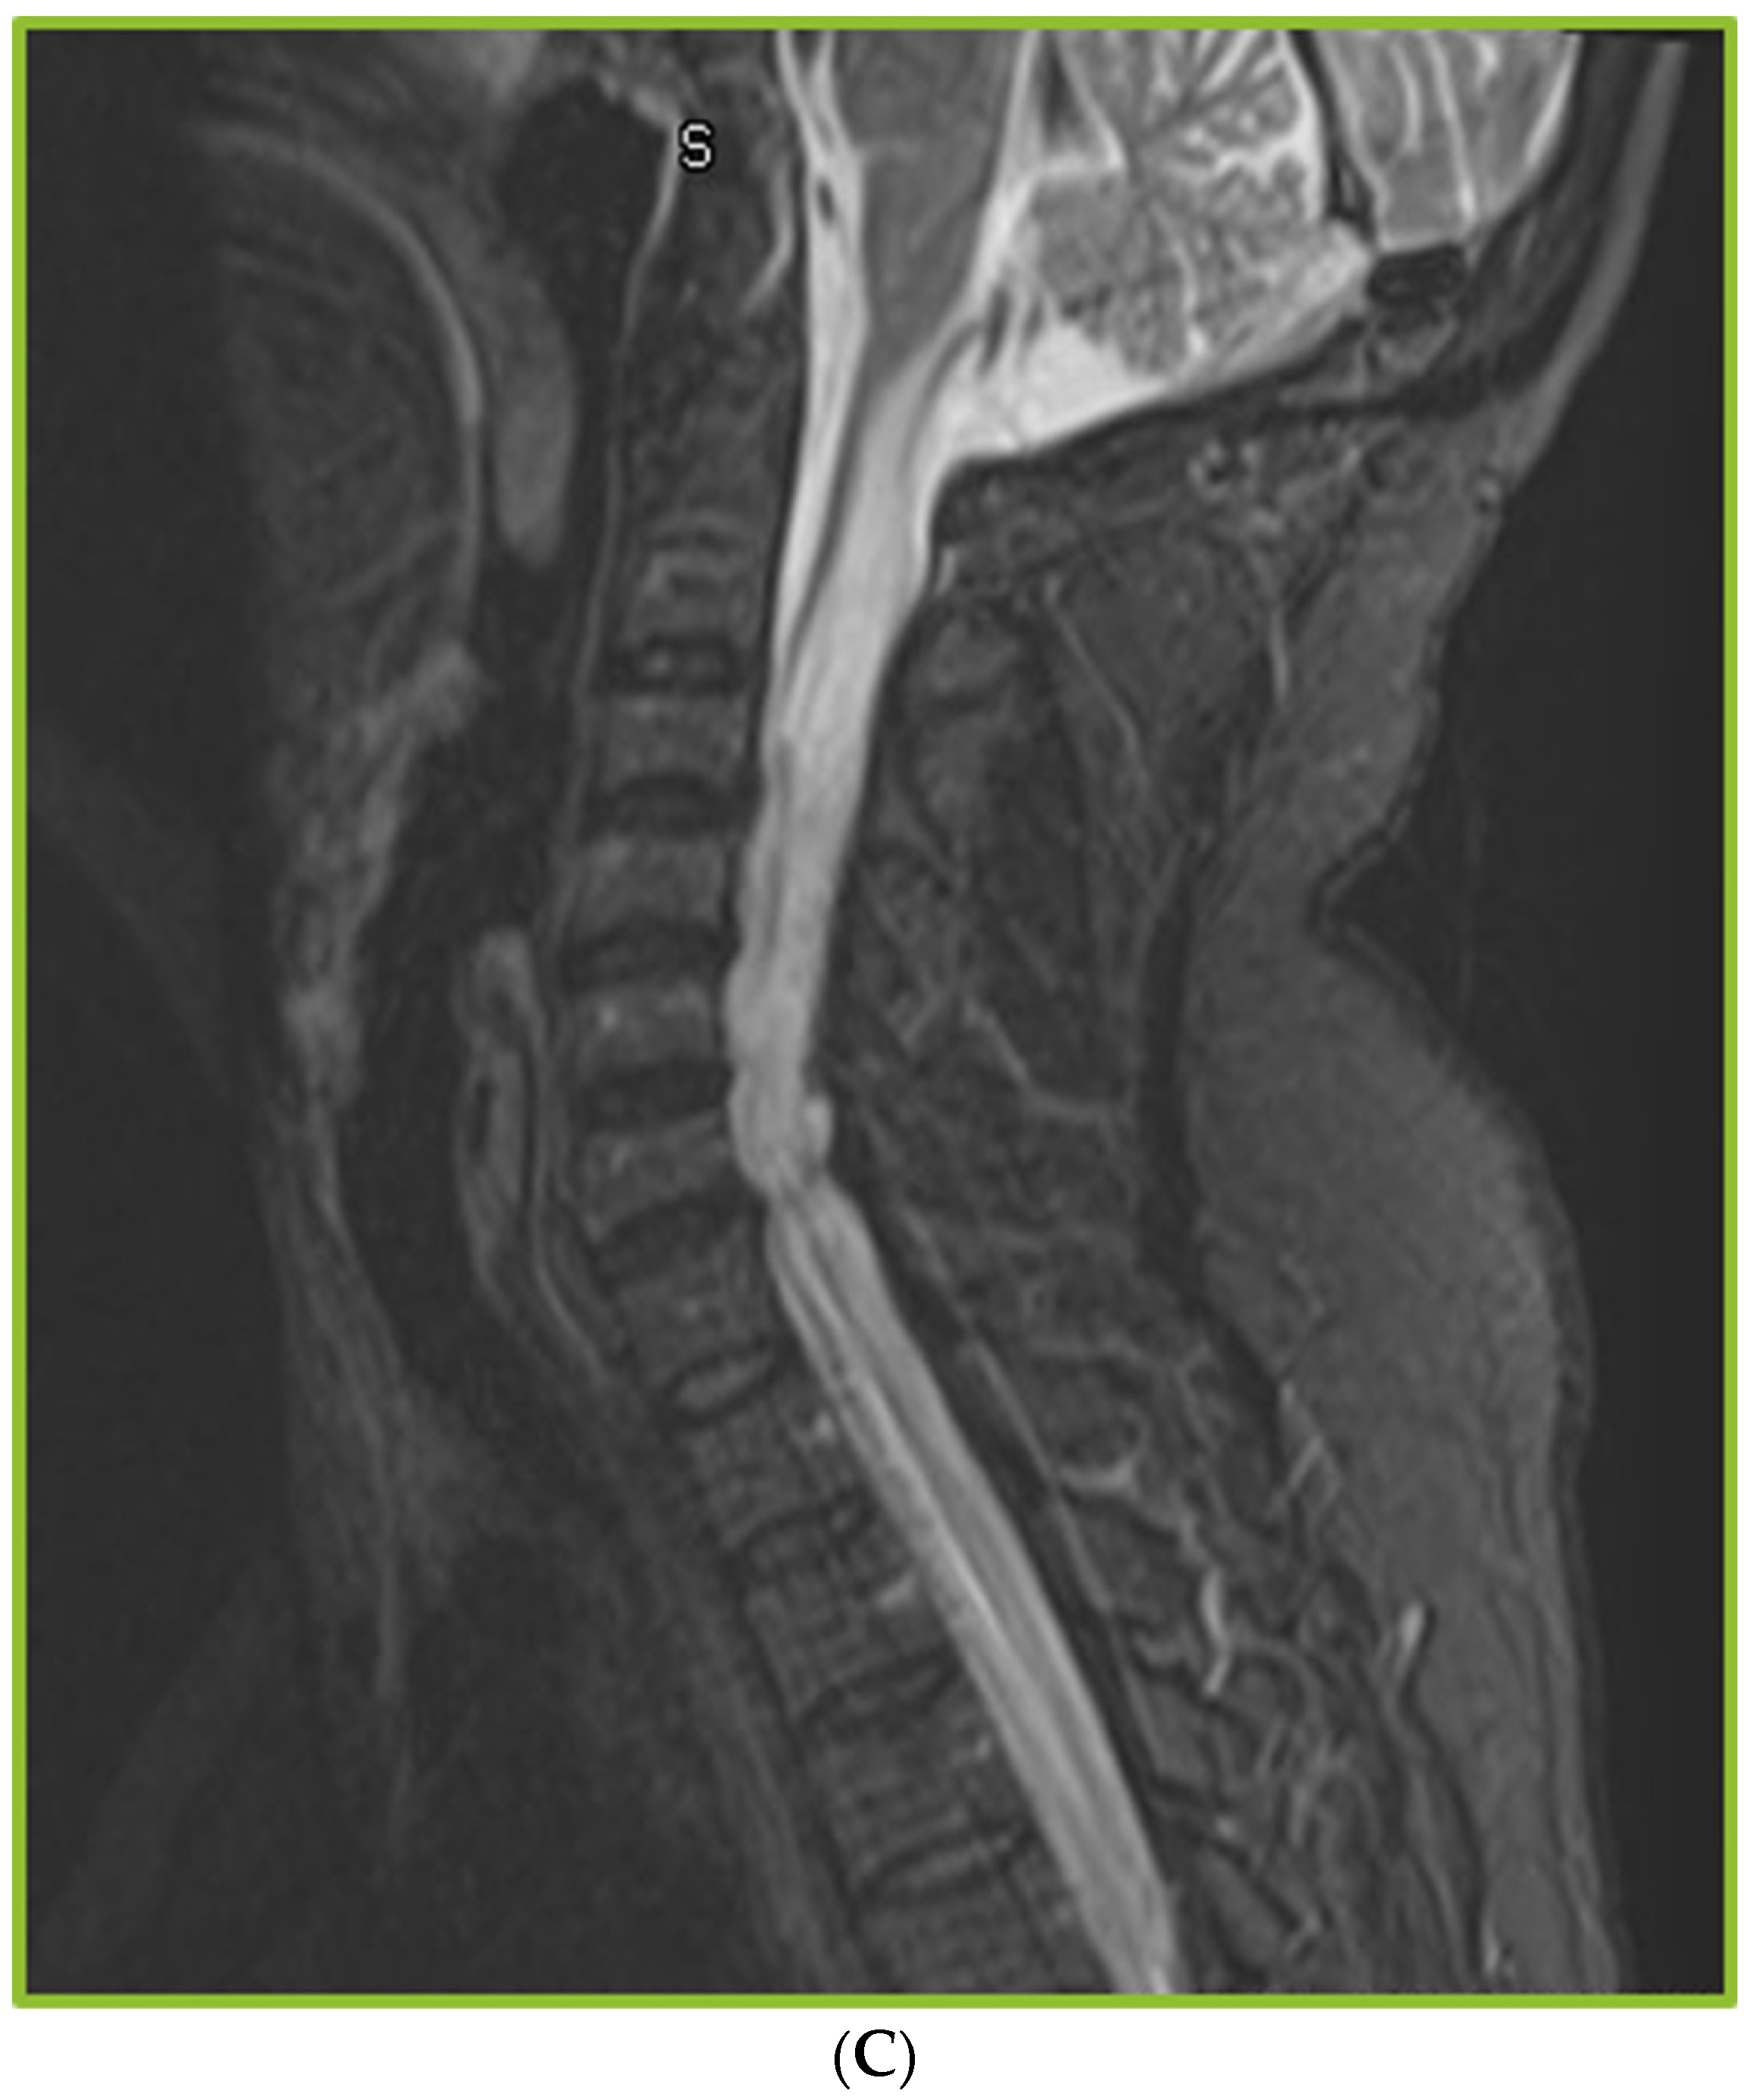

Spinal Arachnoiditis in Patients with Coccidioidomycosis Meningitis—Analysis of Clinical and Imaging Features